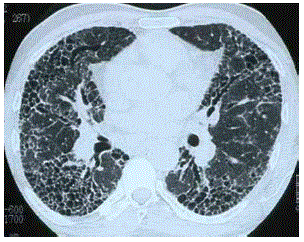

Cistos pulmonares podem ter diversas formas de apresentação, além de poderem aparecer de forma isolada ou um conjunto.

Baseado na imagem disponibilizada, qual o seu diagnóstico?